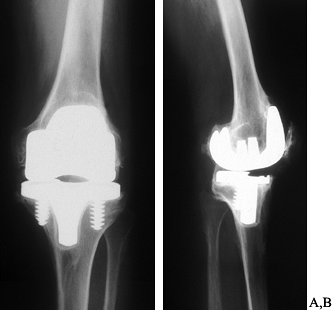

Figure 109.11. Intramedullary stem extensions. A,B:

Fully cemented nonmodular stem with the original Total Condylar III (Howmedica, Rutherford, NJ) femoral component, used here because of poor bone quality with a posterior stabilized nonmodular tibial component. C: Fully cemented fixed stem extension with a constrained articulation. D: Press-fit modular stem extension with methacrylate cement applied only to the component. Note the nonconstrained posterior stabilized prosthesis. The femoral stem extension is undersized relative to the medial lateral dimension of the endosteal canal—it does not, however, compromise the alignment of the prosthesis. The tibia, by contrast, fills the canal but as a result lies in valgus. E,F: AP and lateral radiographs of fully cemented, 145 mm stem extensions. Note the constrained articulation. These are indicated in the presence of poor quality bone when constrained prostheses are used. G,H: AP and lateral radiographs of a constrained articulation, necessitated by medial collateral ligament incompetence with fully cemented, short or “stubby” stem extensions. I: Loose noncemented femoral stem extension. Note the constrained articulation, which most likely contributed to the loosening and the increased valgus alignment resulting from the tight press-fit of a straight stem in an asymmetric bone. J: Offset stems, used without cement. Note the tight fit in the canal without compromising the alignment of the arthroplasty. This revision was performed for instability, and accordingly, a larger femoral component was selected. K,L: Extremely long uncemented stem used in a second reimplant for sepsis in a patient who had already failed one two-stage reimplantation. These very long stems have been used to stabilize large structural allografts and should never be fully cemented. |